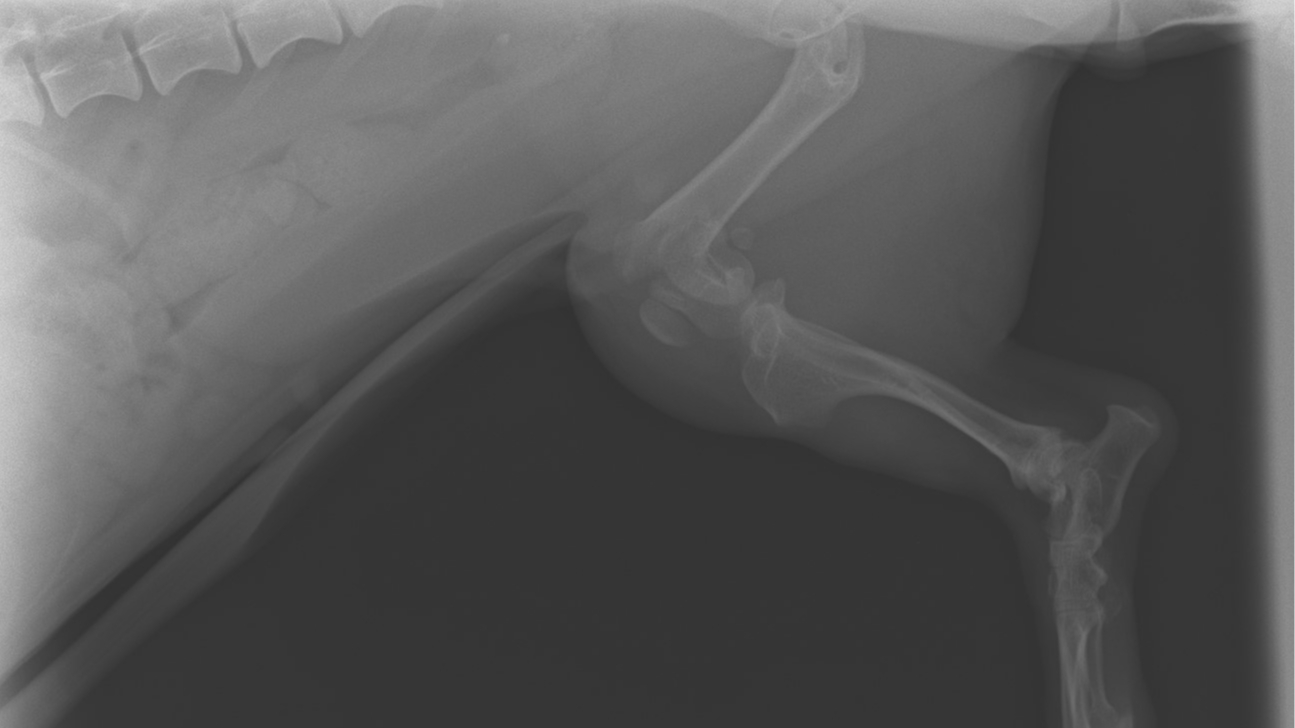

DJ the sausage dog has gotten into an accident and has broken a leg. Het owner is unable to pay for her vet fees to fix it, so she's been taken into the care of Wiener Crew Rescue. The funds raised by you wonderful people will go directly to DJ's vet bill which has been quoted at $6000 We're only a small rescue, and need the help of others in cases like this. We'll share DJ's recovery journey as much as we can. Thank you so much for donating, and please share!